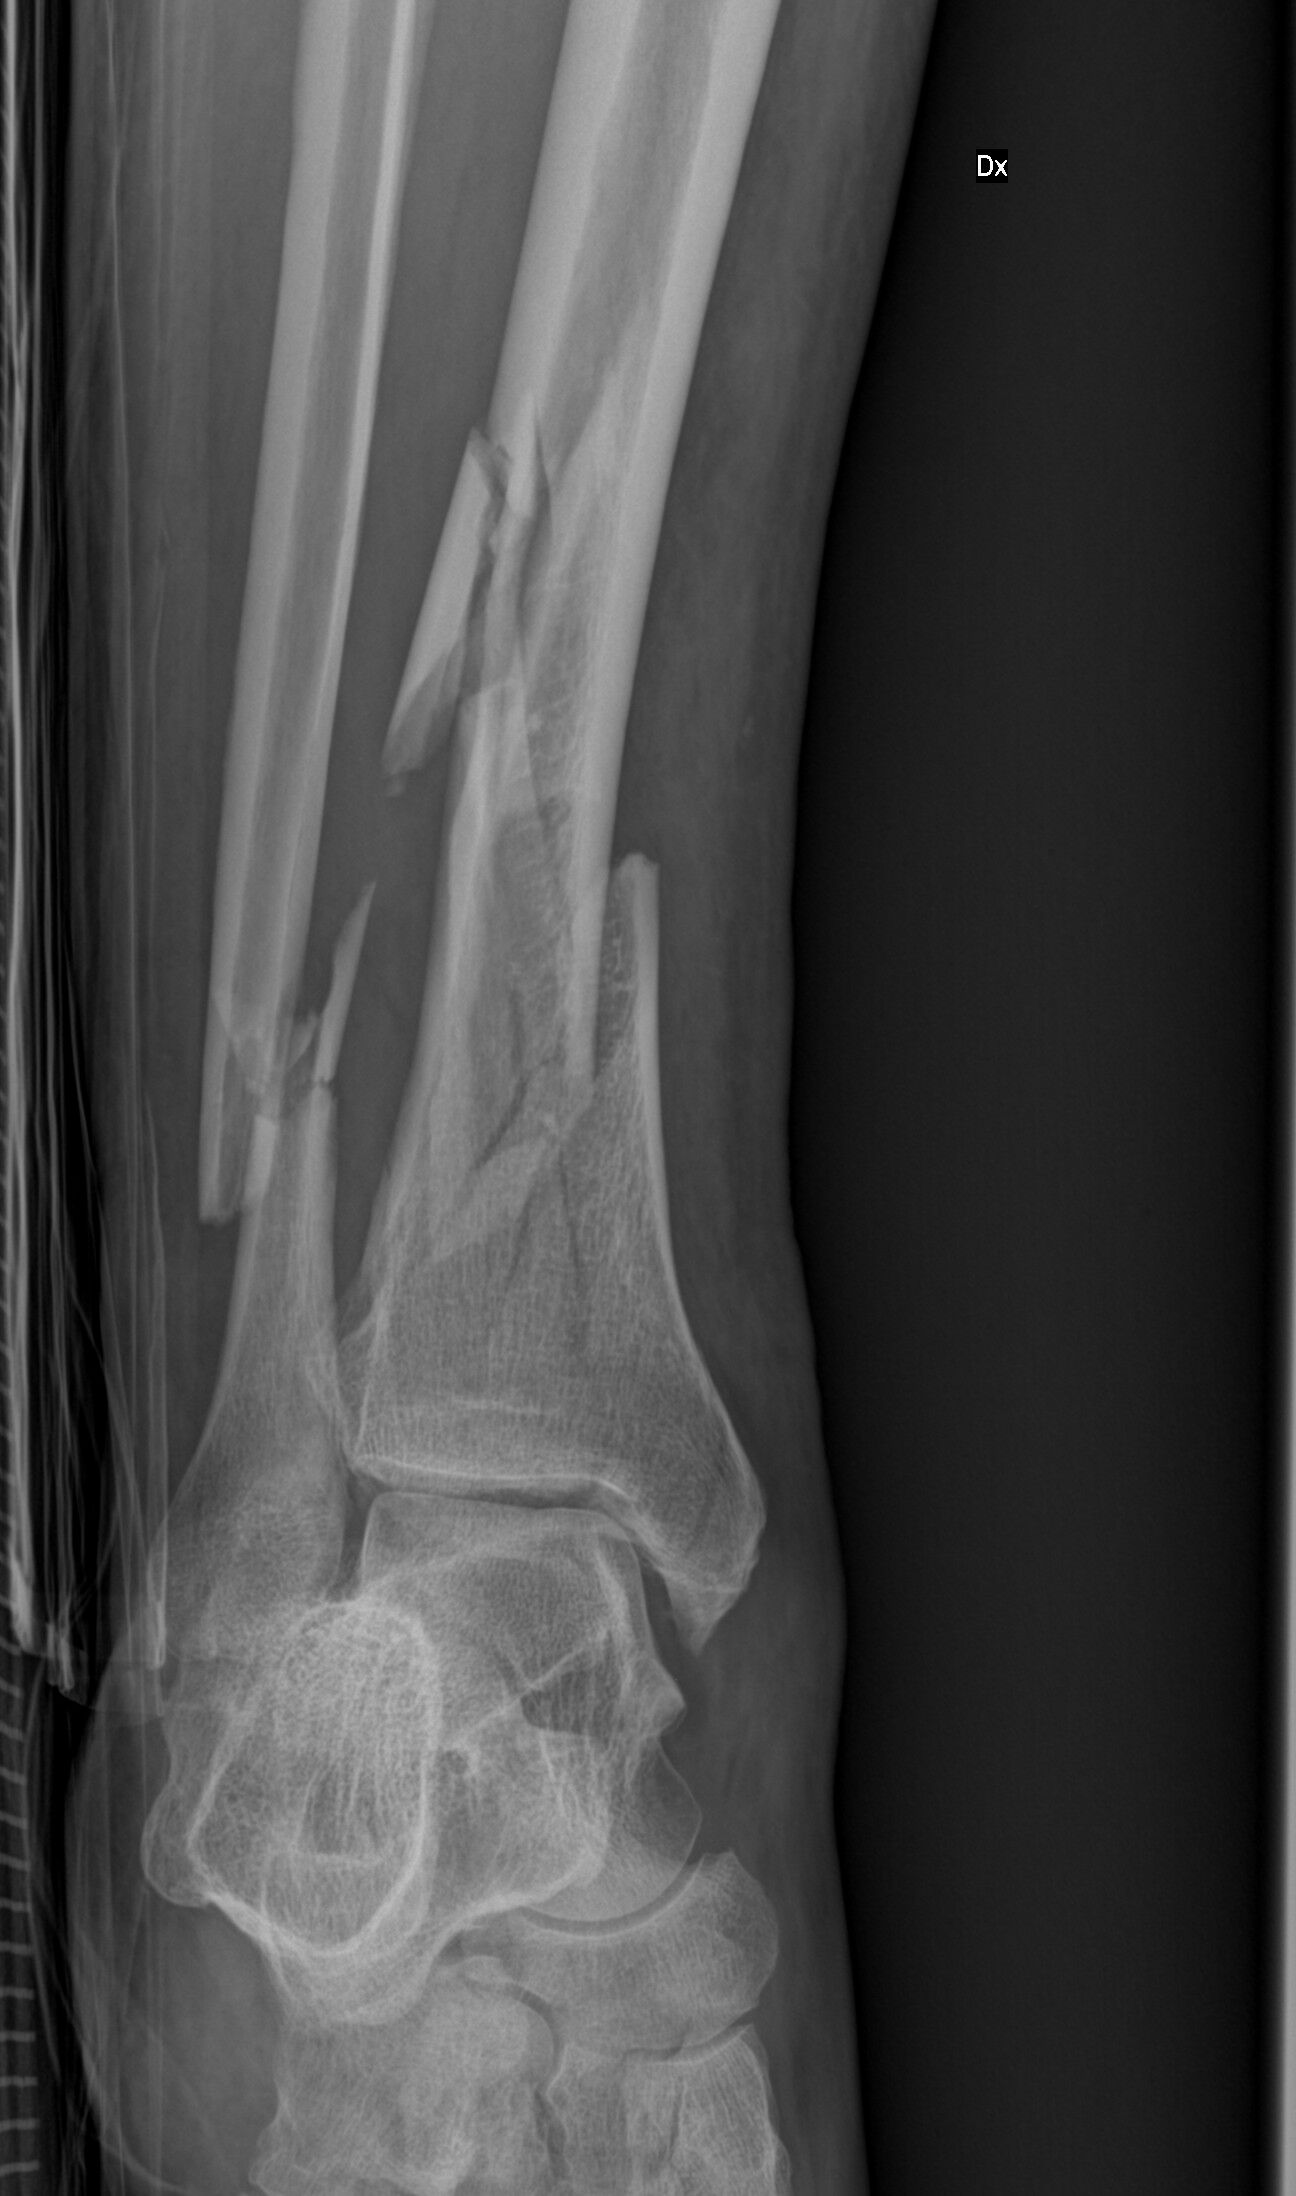

6. Dnes mi ortoped v Prostějově řekl,že je to mistrovská práce,že to nedělal ortoped,ale umělec. Jinak,příští rok se pokusím dojet domů bez pomoci sanitky.Mimochodem,v kůlně nestojí,ale v teple doma. A nestojí ani v šopě!!!!! Źe Bobe

8. Pokud správně počítám,tak 15. Ale řekl bych ,brilantní práce.

9. Kdyby měl případný místní ortoped zájem o foto výsledku italských chirurgů,tak sem dám fotku.

10. Tak už jsem po malém intermezzu na ortopedické klinice v Cres taky zpět.Trošku jsem se zakryl motorkou a noha nevydržela.Lepší místo jsem si snad ani nemohl vybrat.Velká lyžařská oblast Val di Sole,kde spravovaní nohou je jejich denní chleba.A když je zrovna v práci specialista a primář v jedné osobě,tak to nemá chybu.